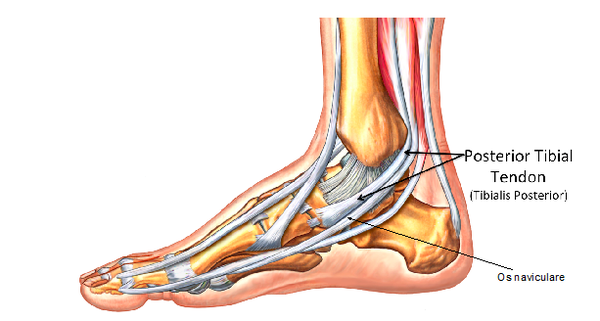

FDL Tendon transfer

The torn tendon would consequently be replaced by a nearby tendon (flexor digitorum longus tendon FDL). This tendon can be used without greatly affecting lesser toe function as there is another tendon which performs almost the same job within the foot.

FDL would be used to replace the torn tibialis posterior tendon. The FDL muscle and tendon is approximately one third of the size of tibialis posterior. Consequently, performing this procedure in isolation would fail to provide long term stability and correction.